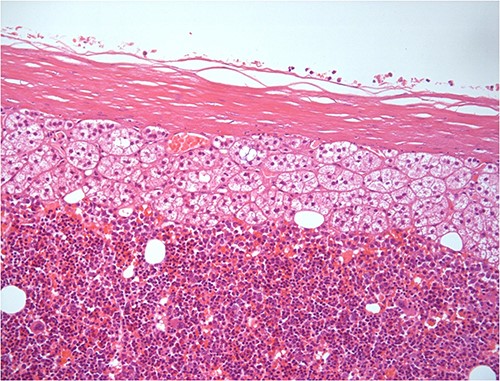

H–E ×200 hematopoietic elements including megakaryocytes with some lipocytes. Above there is a rim of compressed adrenal cortical tissue and fibrous capsule of the adrenal.

On histopathologic examination, myelolipomas are predominantly composed of mature adipose tissue with interspersed hematopoietic tissue components. These fatty elements and hematopoietic areas may be clearly separated, or they are often intermixed.